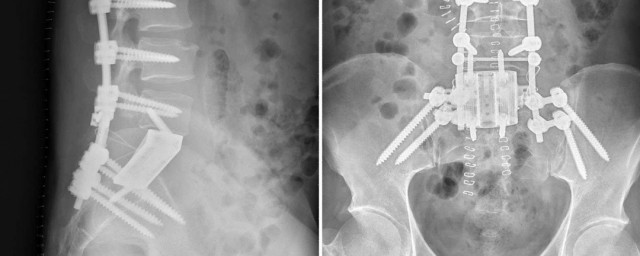

1、骶骨位于身体的中下部,是骨盆环的重要组成部分,位于脊椎的偏下方。脊椎主要有颈椎、胸椎、腰椎、骶椎等构成,骶椎与两边的髂骨,坐骨,耻骨构成骨盆环,起到保护和力传导的作用。骶骨一般在皮带水平和身体后正中央纵线交点下方,为扁平状骨结构,内有神经从椎间孔发出,骶骨极易发生骨折,一般多由巨大暴力所引起,产生症状时,需要行手术方式进行治疗。